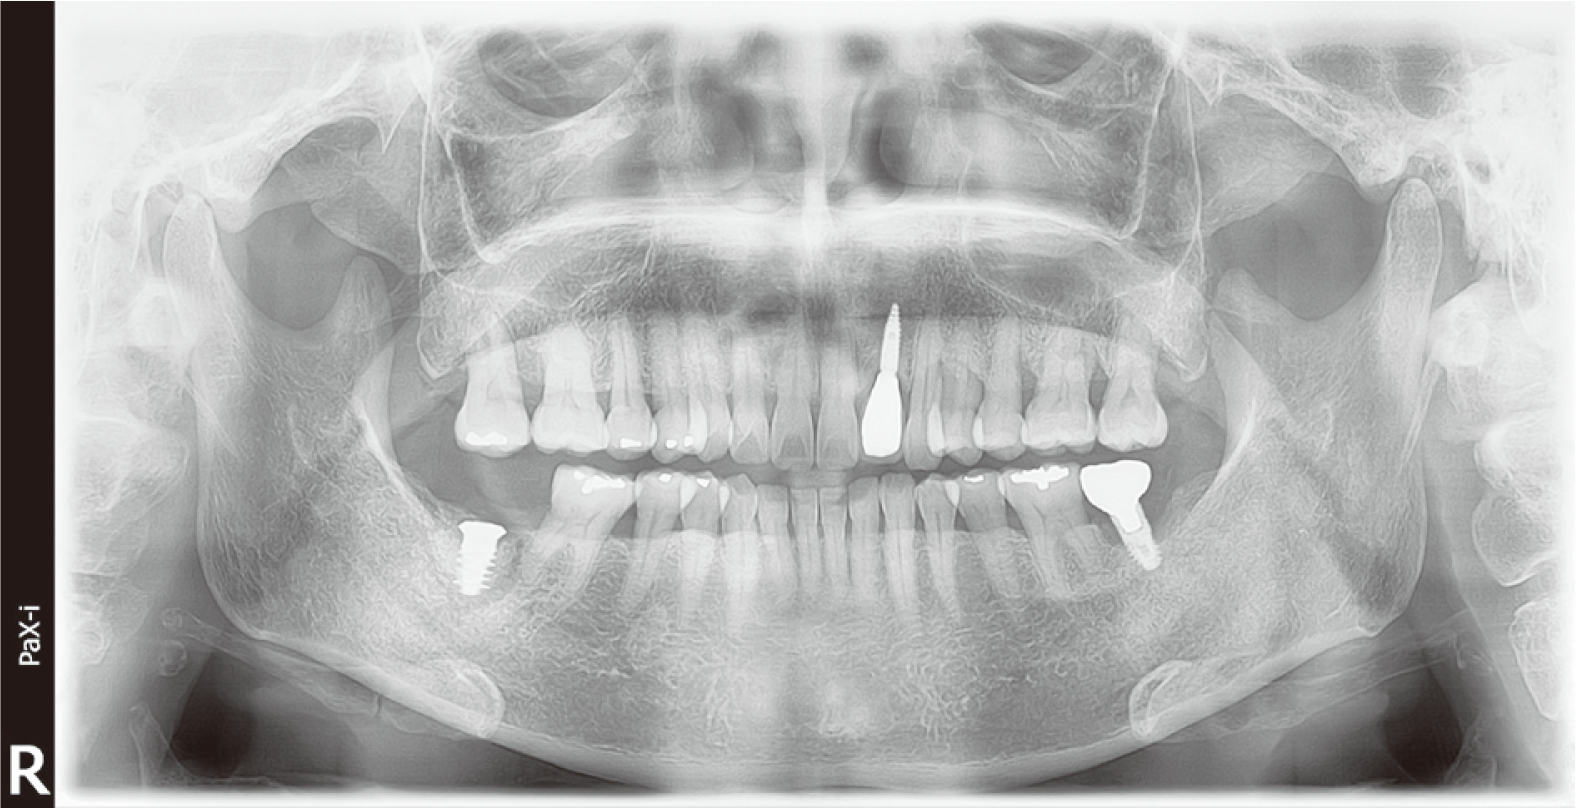

60세 남자 환자로 전체적인 치과치료를 위해 본원에 내원하였다. 환자는 의과적으로 기질성 정신장애를 진단을 받았으며, 거동이 불편하고 보행이 불가능하여 요양병원에서 입원 치료 중이었다. 정신건강의학과에서 환자의 정신장애에 대해 치료상태가 안정된 상태임을 확인한 후, 치과치료를 진행하였다. 파노라마 방사선 사진 및 구강검사에서 상악 우측 제1소구치와 제1대구치, 좌측 제제1, 2소구치, 하악 우측 제1대구치에 잔존 치근이 존재하였으며, 상악 우측 견치와 하악 좌측 견치 및 소구치에서 치아우식증이 관찰되었다(Fig. 1). 환자의 의과적 병력과 치료의 협조도, 구강위생 조절 능력 등을 고려했을 때, 가철성 보철물의 유지와 관리가 어렵다고 판단되어 고정성 보철물로 수복을 계획하였다. 예후가 불량한 상악 우측 견치, 제1소구치, 제1대구치와 좌측 제제1, 2소구치, 하악 좌측 견치, 제1소구치와 우측 1대구치를 발치 한 후, 치아 상실부위에 임플란트 식립을 하였고(Fig. 2), 골유착 기간을 거쳐 최종인상을 채득하였다. 제작한 임플란트 보철물을 장착하던 과정에서 치과의사는 하악 우측 제제1, 2소구치와 제1대구치로 이루어진 3본 지르코니아 보철물이 환자의 구강 내로 떨어뜨렸고, 떨어진 즉시 환자의 두부를 좌측으로 돌려 환자가 보철물을 삼키지 않도록 노력하였으나, 환자가 보철물을 삼키게 되었다. 환자가 보철물을 삼킨 이후 기침이나 구토 반사 등의 특이적 소견을 보이지 않았으며, 호흡상태는 양호하였다. 환자 보호자에게 보철물 장착과정에서 보철물을 구강 내로 떨어뜨렸고, 이후 삼킴이 발생하였음을 설명하였다. 그리고 삼켜진 보철물의 위치 확인을 위하여 인근 내과로 전원 의뢰를 시행하였다. 전원 의뢰된 당일, 내과에서 복부 방사선 사진을 촬영하였고, 판독 결과 보철물이 위장에 위치를 하고 있음을 확인하였다. 24시간 이후 배출될 것으로 예상되어 48시간 후 재촬영이 필요할 것이라는 회신서를 확인하였다(Fig. 3). 2일 후 환자를 내원하도록 하여 추가로 복부 방사선 사진을 촬영하였다. 방사선 사진에서 위장관 내에서 보철물 확인되었다. 환자의 거동이 불편하여 위장관 운동이 저하되어 있는 상태이기 때문에 배출이 지연될 수 있다는 의과적 소견을 회신 받았다(Fig. 4). 8일 후 환자의 복부 방사선 사진을 촬영하였으며, 보철물이 위장관에서 완전히 배출되어 체 내에 있지 않음을 확인하였다(Fig. 5). 이 후 하악 우측 제1, 2소구치와 제1대구치에 새로운 보철물을 제작하여 최종 합착(Rely-X, 3M ESPE, St Paul, USA)을 시행하였다(Fig. 6).

59세 여자 환자로 심한 치주염으로 예후가 불량한 하악 우측 제2대구치 발치 및 임플란트 식립을 위해 본원에 내원하였다(Fig. 7). 하악 우측 제2대구치를 발치하고 임플란트 식립하였다(Fig. 8). 골유착기간을 기간을 거쳐 임플란트 최종인상을 채득하였다. 하악 우측 제2대구치 임플란트 부위에 맞춤 지대주와 상부 임시 치관을 장착하였고, 적응도를 평가하기 위해 경과 관찰을 시행하였다. 4일 후 환자가 상부 임시 치관을 분실하였다고 내원하였다. 환자는 식사 시에 임시치관이 탈락한 느낌이 없었으며, 기상 시에 갑자기 없는 것을 확인한 것으로 보아 취침 중에 삼킨 것 같다고 하였다. 단일 임시 치관의 형태와 크기, 방사선 불투과성에 대해서 설명하였고, 삼켰을 경우 나타날 수 있는 합병증의 가능성을 설명한 후, 인근 내과로 전원 의뢰하였다. 내과에서 촬영한 복부 방사선 사진에서 임시치관을 관찰할 수 없었으며(Fig. 9), 임시치관 재료의 방사선 불투과성으로 인해 나타나지 않을 수도 있음을 추가로 설명하였다. 환자에게 일주일 정도의 경과 관찰이 필요함을 설명하였고, 그 기간 동안 특이 소견이 없음을 확인하였다. 이 후 최종 보철물을 제작하여 합착(Rely-X, 3M ESPE)을 시행하였다(Fig. 10).